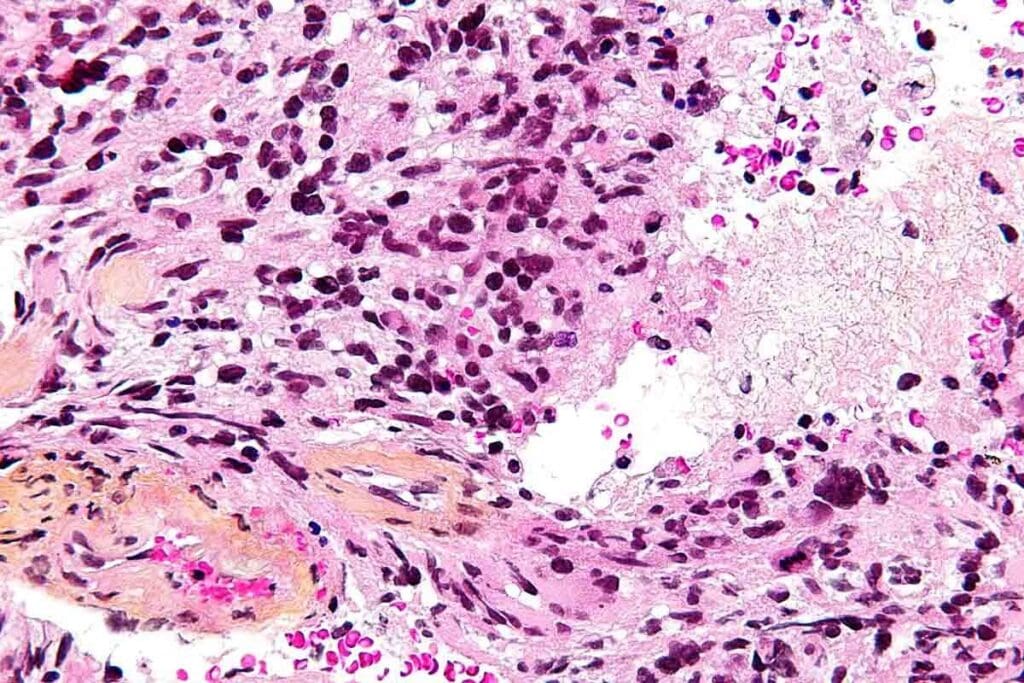

Biopsy and Histopathological Evaluation

A biopsy is key to confirming GBM. We take tissue samples during surgery. Looking at these samples under a microscope helps us spot the tumor’s unique features.

Cellular and Molecular Characteristics

Pediatric glioblastoma multiforme grows fast and is very aggressive. It has many cell types, including stem-like cells. These cells help the tumor fight off treatments as studies show.

The tumor’s genes and epigenes change a lot. These changes mess with signals that control cell growth and survival. For example, TP53 and PTEN gene mutations are common in GBM, making it very bad.